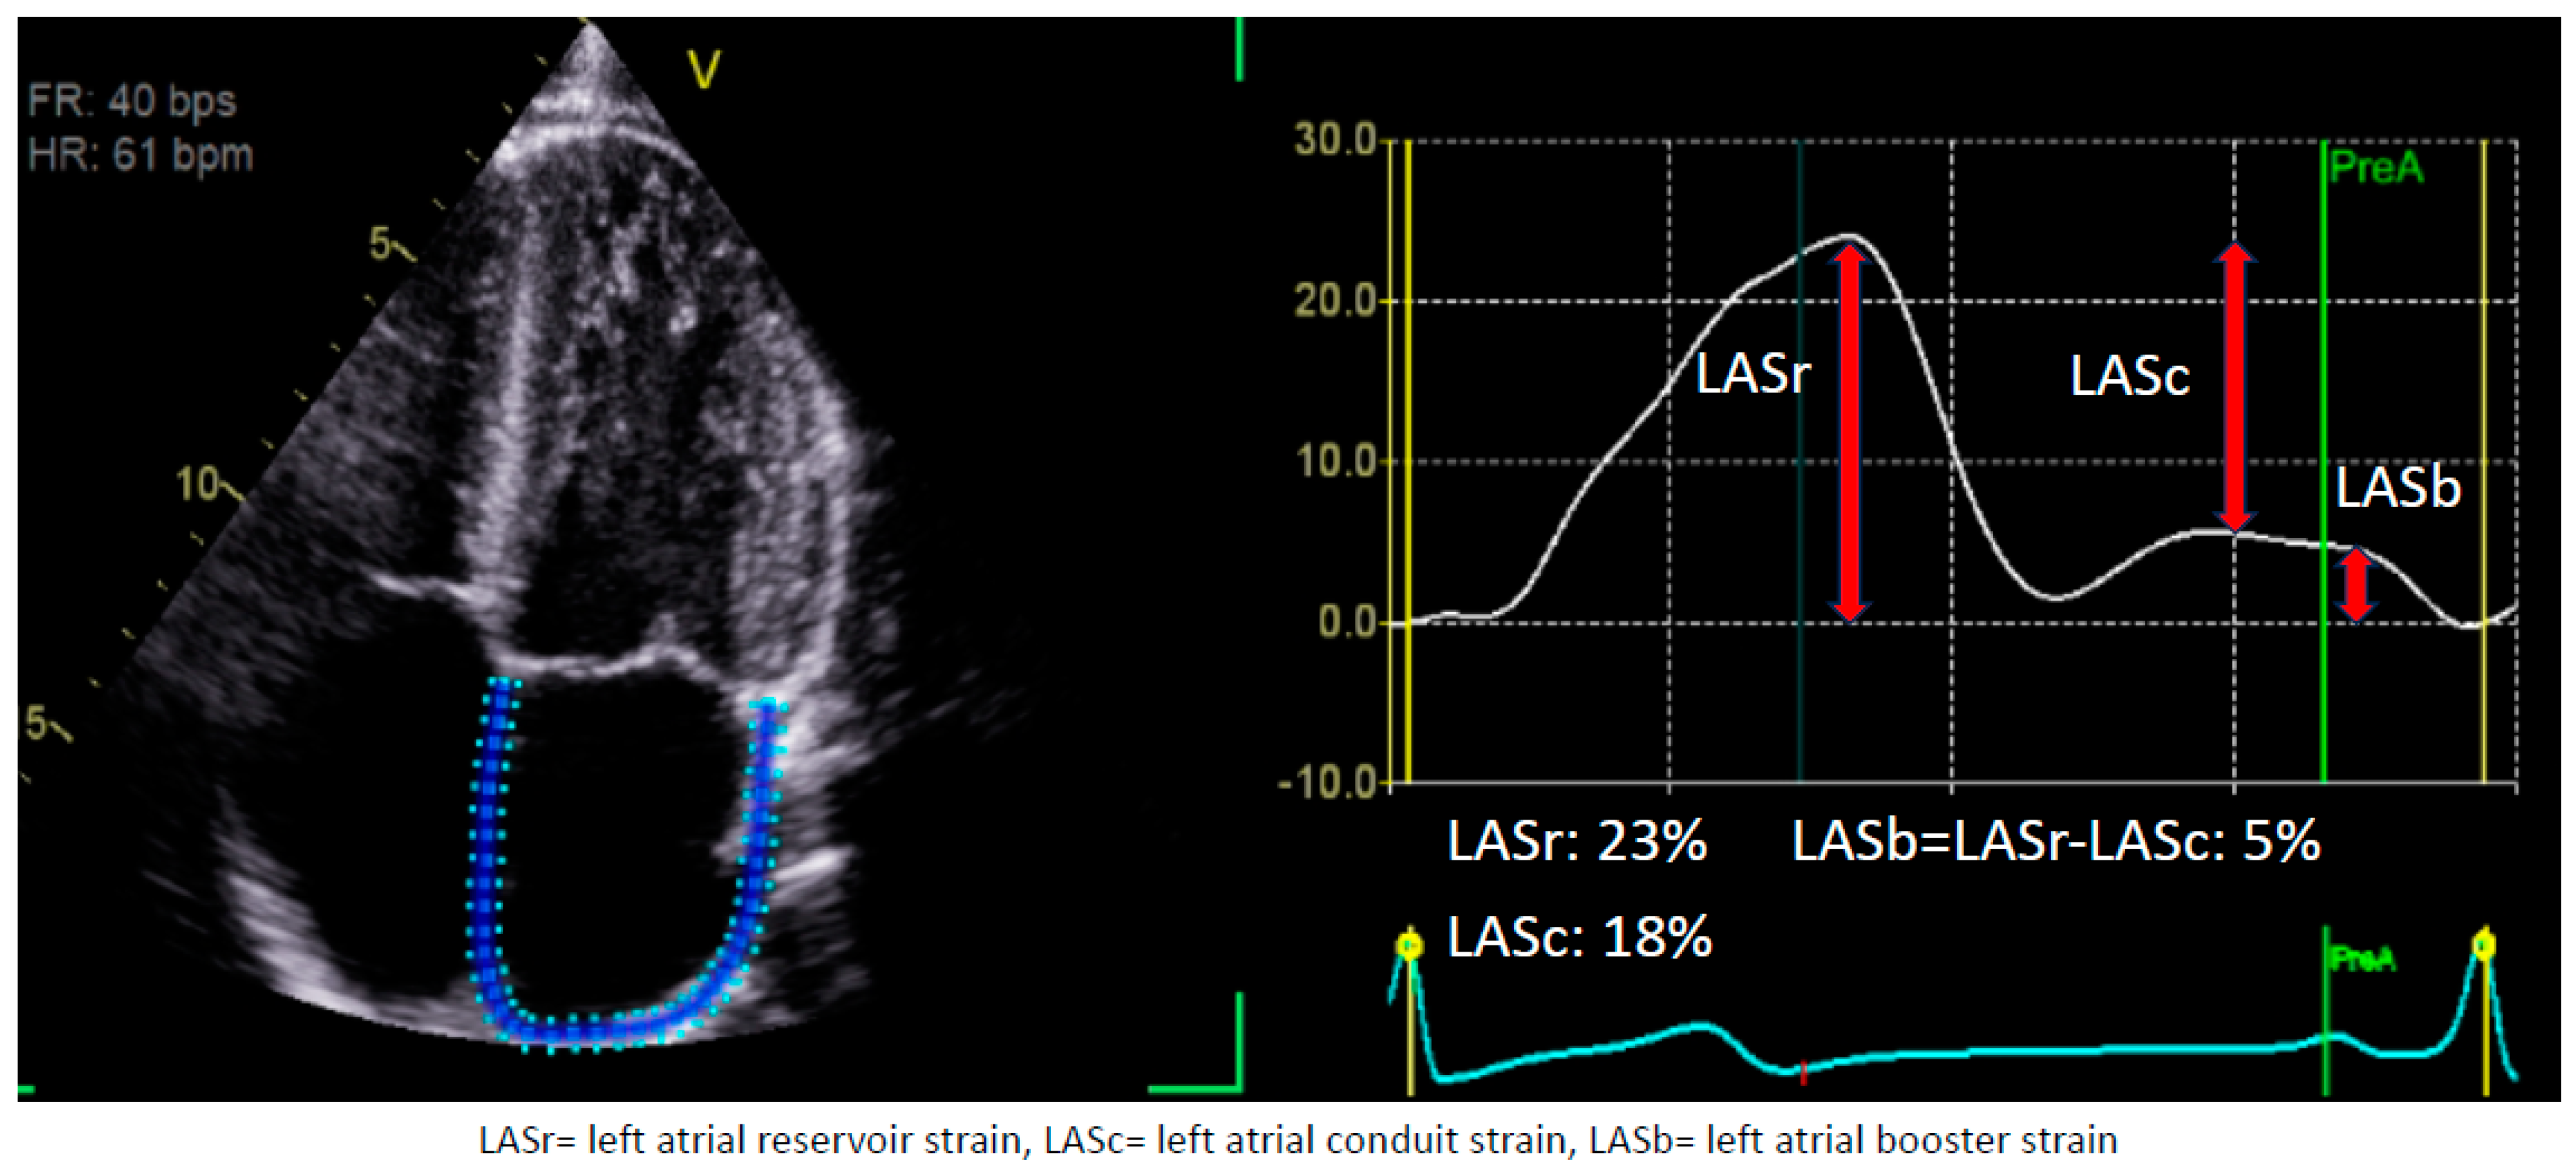

1.1. Assessment of LA Strain